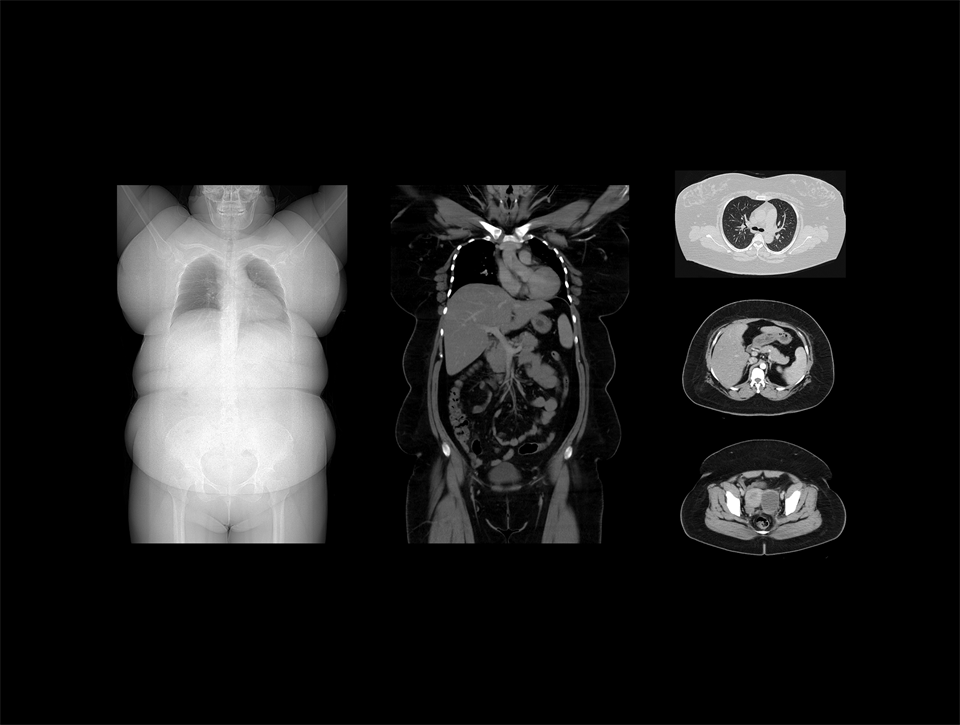

Algoritm bazat pe inteligență artificială care permite imagistica pe întreaga dimensiune a gantry-ului și elimină artefactele de trunchiere.

Gantry ultra-larg de 82 cm

Deschiderea generoasă de 82 cm oferă pacienților o experiență de examinare confortabilă și un spațiu de lucru flexibil, îmbunătățind în același timp capabilitățile imagistice pentru pacienții bariatrici.

Gantry-ul ultra-larg de 82 cm permite poziționarea flexibilă a pacienților bariatrici.